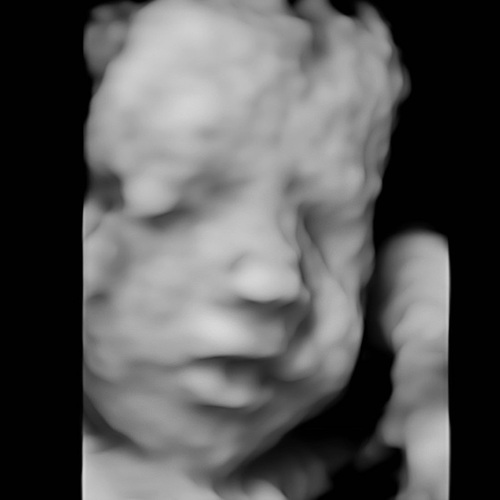

Hier ligt ze met haar gezicht naar mijn rug te kijken. Inderdaad armen en benen ervoor. Kontje naar beneden. Gister 3/4d echo gehad. Het duurde even. Hebben een paar keer het snoetje gezien maar niet duidelijk!

Aahh wel een gave foto alsnog haha!

Haha ja, later gelukkig ook haar snoetje laten zien😍